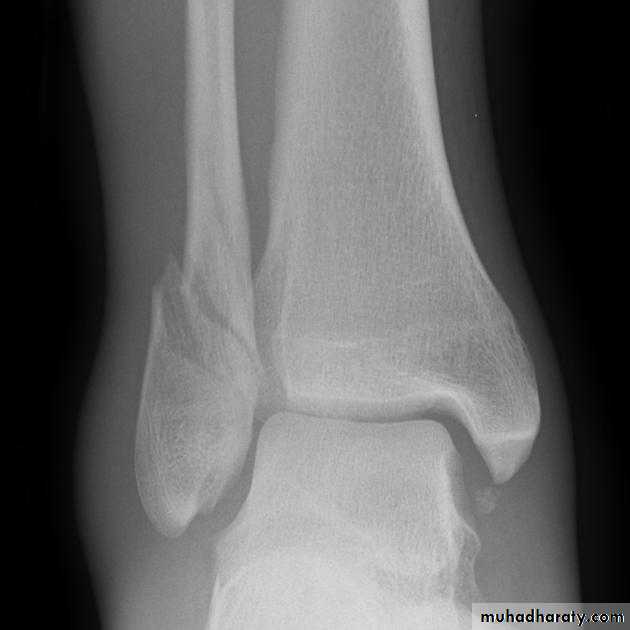

Fractures around the ankle

The bones forming the ankle mortise are injured more often than any other bone except the lower end of the radius. In the past they were often grouped together loosely under the general title is still used occasionally‘ Pott's fracture’.Types:

Fractures ankle

Clinically: there is history of twisting injury of ankle followed by severe pain, inability to stand, swelling, bruises, deformity & tenderness.

X ray: it is essential to do anteroposterior, lateral and mortise views (The AP mortise view is done with the leg internally rotated 15-20o ,This view permits examination of the articular space (clear space). The width of the clear space between the talus and the articular surfaces of the medial malleolus, the tibial plafond and the lateral malleolus should be equal.

X- ray shows the type of fractures, Any shift, tilt or displacement in talus is serious, If the fibular fractures above the tibiofibular joint there must be a diastasis.